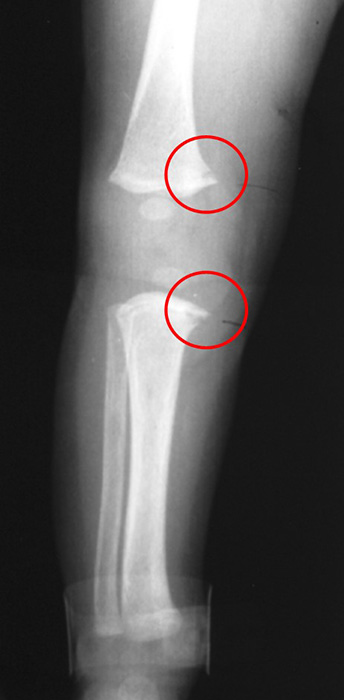

The area of injury are circled on this image of a 4 month old child. What pathology is seen? (Corner fracture)

Non-accidental Injury